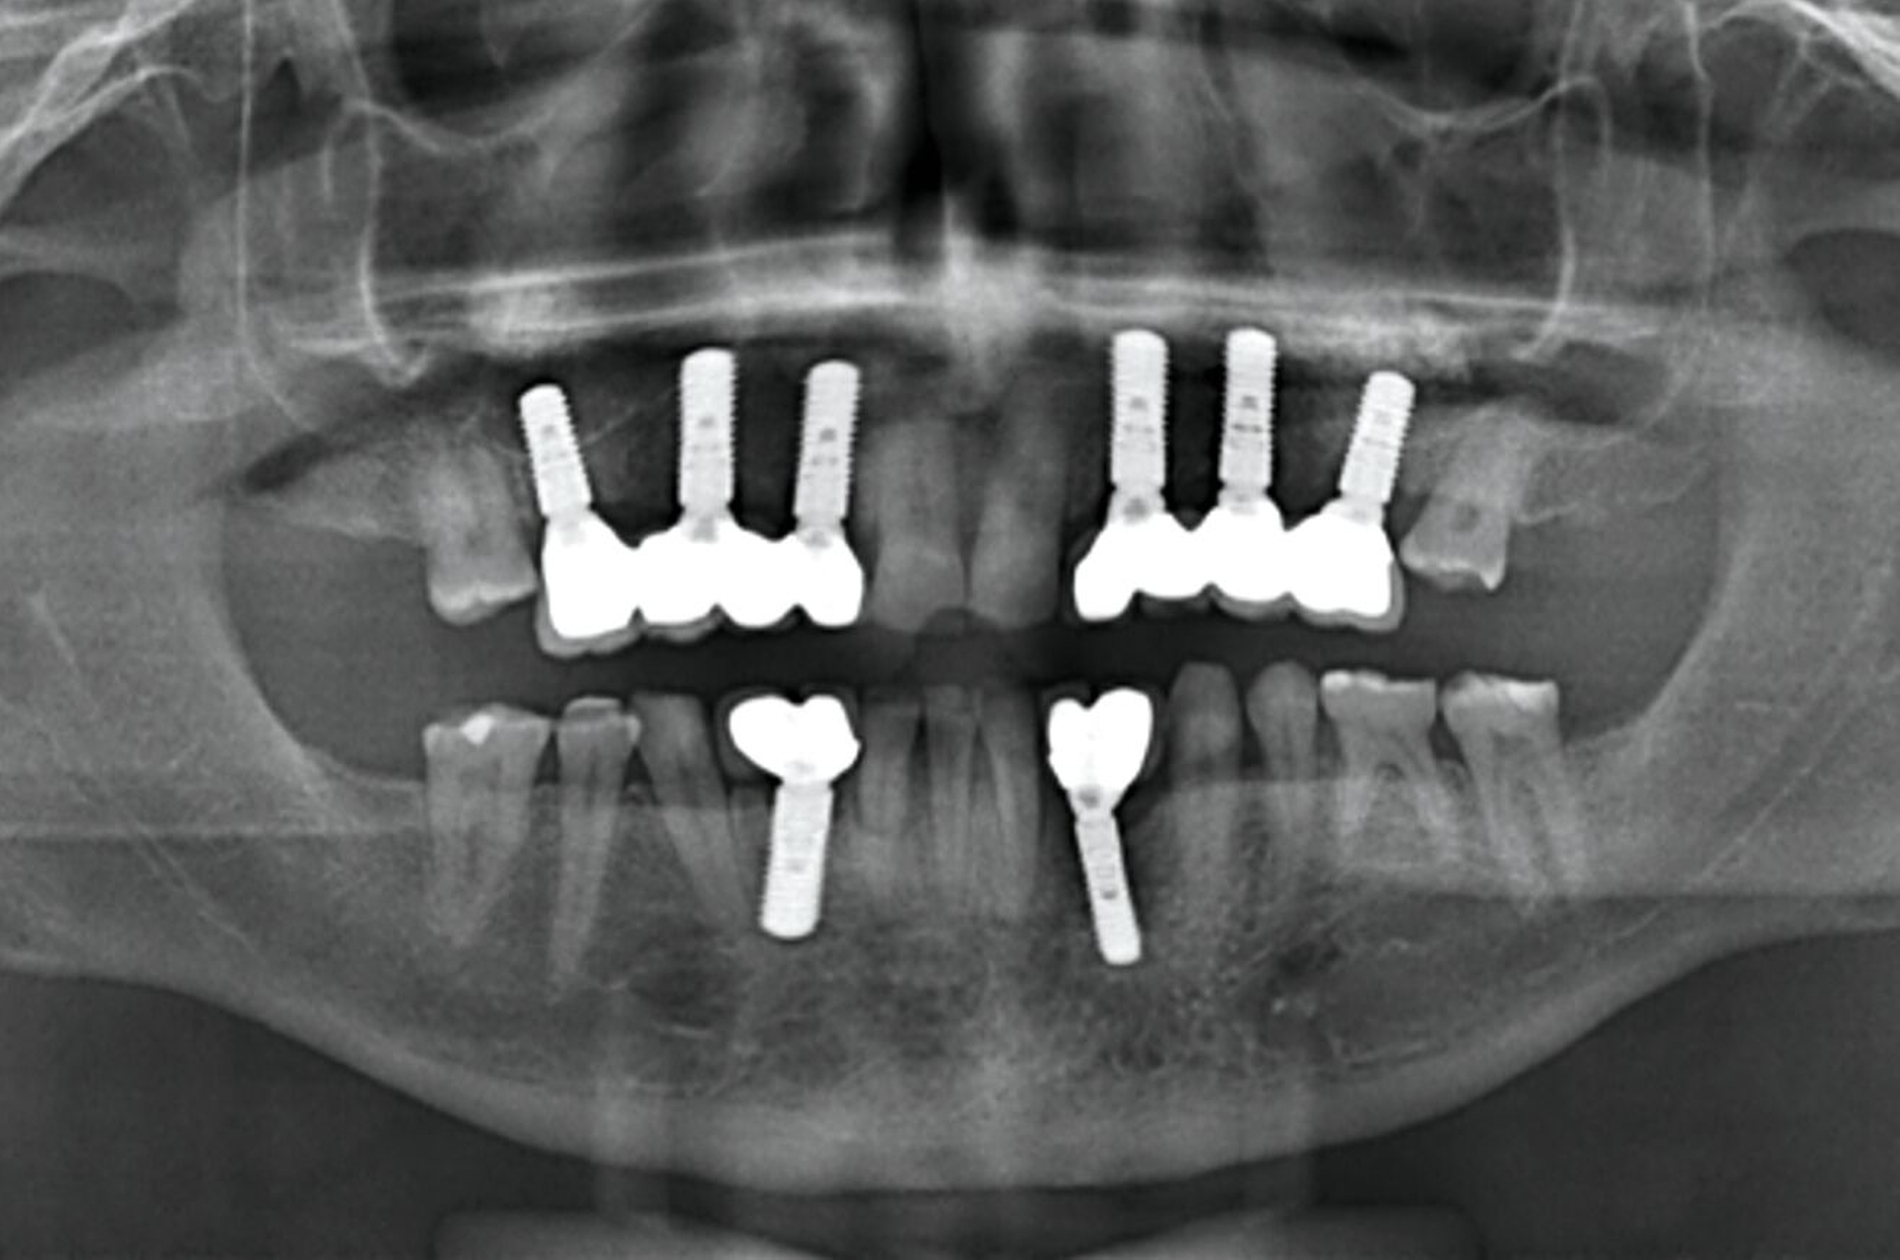

Nach komplikationsfreiem Heilungsverlauf (Abbildung 8) erfolgte die Freilegung der Implantate, die Einsetzung von Gingivaformern und die Anpassung des Interimsersatzes (Abbildung 9). Wegen der dadurch anfallenden zusätzlichen Kosten verzichtete der Patient auf ein Langzeitprovisorium.

Über Abutmenteinproben, Korrekturen der angestrebten Bisslage sowie Gerüst- und Rohbrandeinproben erfolgte die definitive Eingliederung der festsitzenden Versorgung auf den natürlichen Zähnen und den Implantaten. Zehn Monate nach Beginn des mehrzeitigen operativen Vorgehens konnte die komplexe interdisziplinäre Versorgung des Patienten der äußerst ungünstigen Zahn- und Bisssituation nahezu abgeschlossen und zur Zufriedenheit des Patienten finalisiert werden (Abbildung 10).